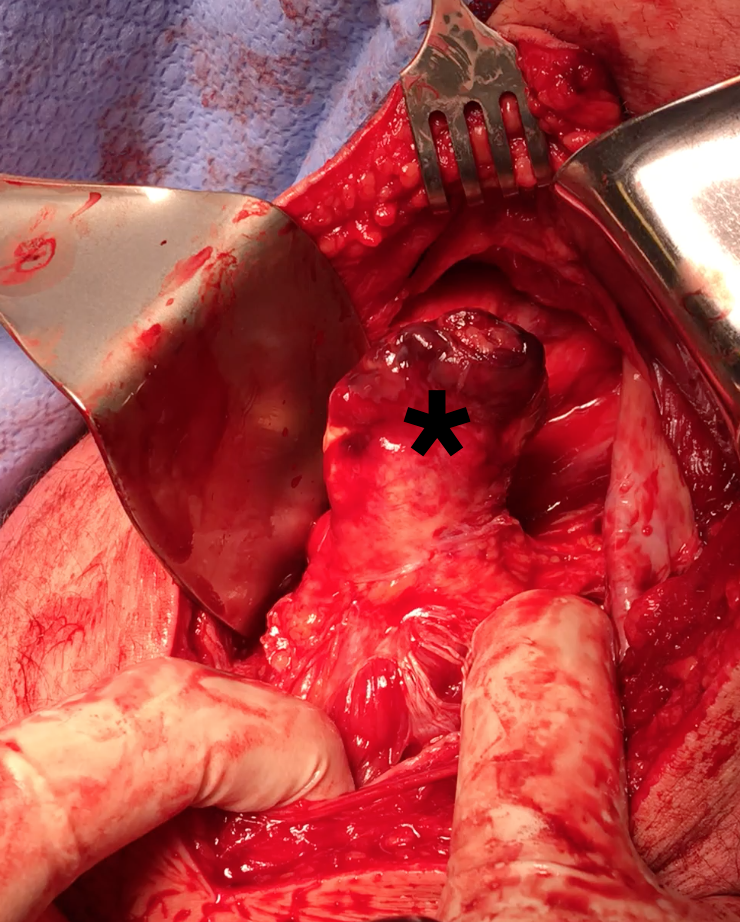

Expose ischial tuberosity

- superior retractor on ischial tuberosity

- medial and lateral retractors, care with sciatic nerve

- use osteotomes to create bleeding

- 2 - 3 suture anchors, double loaded

Exposing ischial tuberosity (*) with Cobb retractor